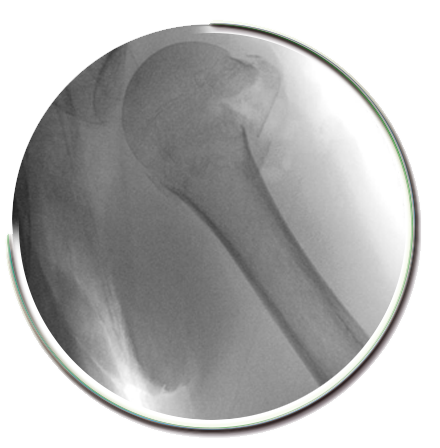

Proksimal humerus, kolun omuz eklemine yakın olan üst kısmının adıdır. Omuz kırığı denilince genellikle proksimal humerus kırıkları kastedilir. Erişkin kırıklarının %5’ ini oluşturur. Genellikle 60 yaş üzerinde, kemik mineral yoğunluğu düşük hastalarda basit düşmeler sonrasında görülür.

Omuz üzerine düşme yada el üzerine düşme sonrasında başlayan şiddetli omuz ağrıları, hareket ettirememe durumu omuz çevresinde kırık olabileceğini düşündürmelidir.

Omuz kırığı tedavisi nedir?

Bu bölge kırıklarının %80’ ini ayrışmamış kırıklar olup cerrahi gerektirmeden tedavi edilebilirler. Tedavide, kol askıları, velpo bandajı, yastıklı askılar gibi basit ve konforlu metodlar kullanılabilir. Yaklaşık 3-6 hafta civarında kol askısı kullanılır. Omuz kırığı kaynama süresi 6 haftadan daha uzun sürse de, ağrısız hareket açıklıklığı kazanılması için fizik tedavi ve rehabilitasyon başlanır.